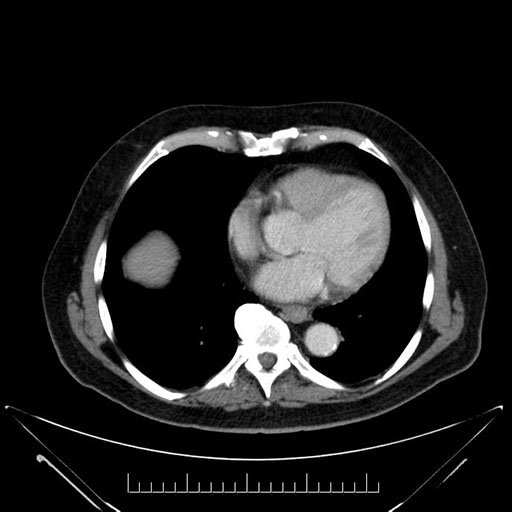

Imaging Analysis

Look through the patient's CT scan to identify any areas of concern for the necessary procedure.

Based on your CT findings, which issue(s) would give reason for "planned slowing down moment(s)" in this case?

Considering a standard Whipple procedure, what step(s) of the operation would you do differently in this case?